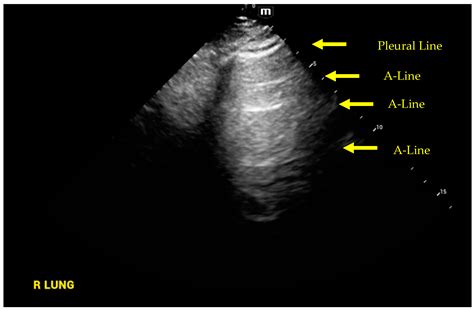

In the context of lung sonography, B Lines Ultrasound patterns are defined as discrete, laser-like vertical hyper-echoic reverberation artifacts. They arise from the pleural line and extend to the edge of the screen, moving in synchrony with lung sliding. Unlike A-lines, which represent normal horizontal reverberations caused by air-tissue interfaces, B-lines signify that the subpleural interlobular septa are thickened by fluid, cells, or fibrous tissue.

When these septa become edematous or infiltrated, they create an acoustic impedance mismatch that traps the ultrasound beam, resulting in the characteristic vertical "comet tail" appearance. Because they move with the visceral pleura, their presence is a highly sensitive marker for the loss of lung aeration.

2. Identify the pleural line—the hyperechoic line moving between the two ribs.

3. Observe the movement of the pleura (lung sliding) to ensure proper positioning.